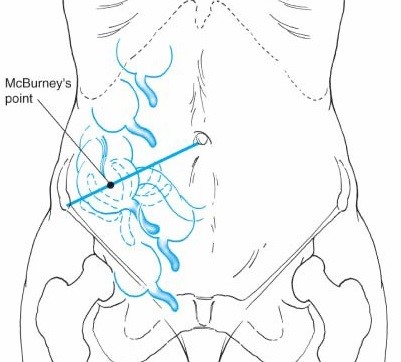

8h18 ngày 25/4/2020 mời ngoại tổng hợp hội chẩn với chẩn đoán tắc ruột. Thăm khám ghi  nhận: đau tức thượng vị và quanh rốn, không sốt,  nôn khan, bụng chướng vừa, chưa trung, đại tiện, không có điểm đau khu trú, hố chậu phải không đau. hình ảnh Xquang không nghĩ đến tắc ruột- cảnh giác VRTC, hẹn khám lại sau 3 giờ. Sau 3 giờ thăm khám lại thấy bệnh nhân có phản ứng vùng hạ vị nghi ngờ 1 tình trạng VRTC tiểu khung. chỉ định siêu âm lại với chẩn đoán VRTC tuy nhiên kết quả siêu âm chỉ cho biết: các quai ruột ứ đọng dịch và phân, giảm nhu động, có ít dịch giữa các quai ruột, ruột thừa hạn chế khảo sát. Bệnh nhân được chỉ định mổ cấp cứu với chẩn đoán VRTC tiểu khung. Tuy nhiên để khẳng định thêm chẩn đoán chúng tôi hội chẩn qua PACS (một phương tiện đọc phim online mà bệnh viện chúng tôi đang sử dụng) hình ảnh CT ổ bụng không tiêm thuốc cản quang ngày 24/4/2020 phát hiện ruột thừa nằm giữa ổ bụng, lòng giảm tỷ trọng, đường kính 10mm, có sỏi phân. Kết luận: VRTC nằm giữa ổ bụng.

2020 05 07 10 52 30

Hình 2. Hình ảnh CT scan 24.4.2020

Trong trường hợp của chúng tôi manh tràng đi vào giữa ổ bụng khiến ruột thừa nằm giữa ổ bụng gây nên các triệu chứng không điển hình như đã mô tả. lần theo manh tràng chúng tôi bắt gặp cấu trúc hình ống đường kính 10mm, thành phù nề, có sỏi phân. Đây là các dấu hiệu có thể kết luận chẩn đoán VRTC. Đây là lợi ích vượt trội của CT so với siêu âm trong chẩn đoán các bệnh lý trong ổ bụng, đặc biệt là các bệnh lý ruột non và đại tràng. CT có thể giúp chúng ta tìm ra manh tràng và đại tràng lên bằng cách lần theo các quai ruột non. CT cũng có thể phân biệt ruột già và ruột non bằng cách chỉ ra các van conniventes hay haustrae. Trong trường hợp ruột quay bất toàn dẫn đến ruột thừa nằm ở vị trí bất thường, CT sẽ giúp ích cho chẩn đoán bằng cách chỉ ra mối quan hệ giữa động mạch và tĩnh mạch mạc treo tràng trên [3]. Như vậy CT là một phương tiện hữu hiệu để chẩn đoán VRTC khi ruột thừa ở các vị trí bất thường như trong trường hợp đảo ngược phủ tạng, ruột quay bất toàn hay manh tràng quá di động như trong trường hợp của chúng tôi.